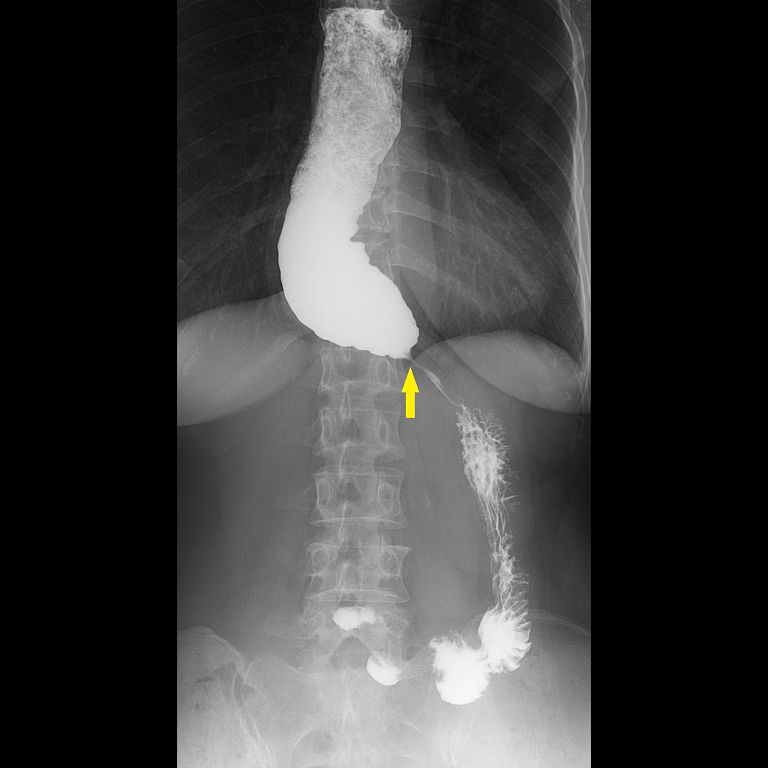

60歲蕭女士多年來飽受進食後胸口悶脹、食物卡在胸口的不適所苦,症狀持續數年卻始終未能明確診斷。輾轉來到台北慈濟醫院後,首先接受食道攝影與食道高解析度壓力檢測(HRM),其中食道攝影顯示食道末端出現典型「鳥嘴狀」狹窄,但壓力檢測結果卻沒有典型下食道括約肌壓力上升表現,讓診斷一度陷入兩難。台北慈濟醫院胃腸肝膽科詹崴宇醫師接著以新式診斷工具功能性管腔成像探頭(Functional Lumen Imaging Probe, Endoflip)檢查,成功確診為「食道弛緩不能症」,讓蕭女士順利進行後續治療。

食道攝影及高解析度壓力檢測是臨床上食道弛緩不能症的標準檢查方式。詹崴宇醫師說明,食道攝影雖可觀察顯影劑流速及食道形狀,也能看到典型鳥嘴狀變化,即胃食道交界過緊而使食物過不去,造成上方的食道因為積壓而擴張,形成如同鳥嘴般的的狀態,但非黃金診斷標準;食道高解析度壓力檢測則是在病人清醒時做吞嚥測試,觀察食道蠕動波形,藉此觀察吞嚥時的壓力是否正常,雖是黃金診斷準則,但臨床上卻有部分病人的檢測結果不明確,導致無法確診,進行後續治療。台灣近來引進Endoflip,是在病人麻醉狀態下,利用氣囊感測器測量食道的擴張性。正常情況下,食道應該像很有彈性的新氣球,只要稍微給點推力就能撐開;但如果食道的彈性變差了,即使氣囊在裡面用力推,食道也動彈不得,將導致食物下不去。這項檢查能補足傳統「食道壓力檢測」難以判讀的死角,提供更精準的數據;加上是在麻醉狀態下進行,大大降低了病患檢查時的恐懼與不適感。